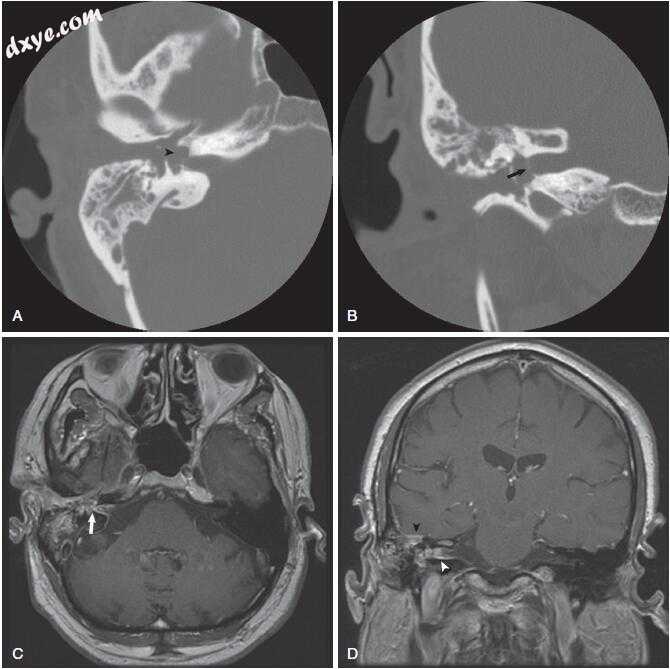

图-14. 影像学表现在急性化脓性迷路炎。 A,颞骨计算机断层扫描(CT)显示慢性乳突炎伴乳突、外耳道和中耳混浊。 注意侵蚀和前庭介入(箭头)。 B,冠状颞骨CT扫描显示内耳道底部的侵蚀和累及(箭头)。 C,轴位对比增强T1加权磁共振成像(MRI)显示中耳,前庭和内听道增强(箭头)。 D,冠状对比增强T1加权MRI显示增强颞叶硬脑膜(黑色箭头)和内听道(白色箭头)。